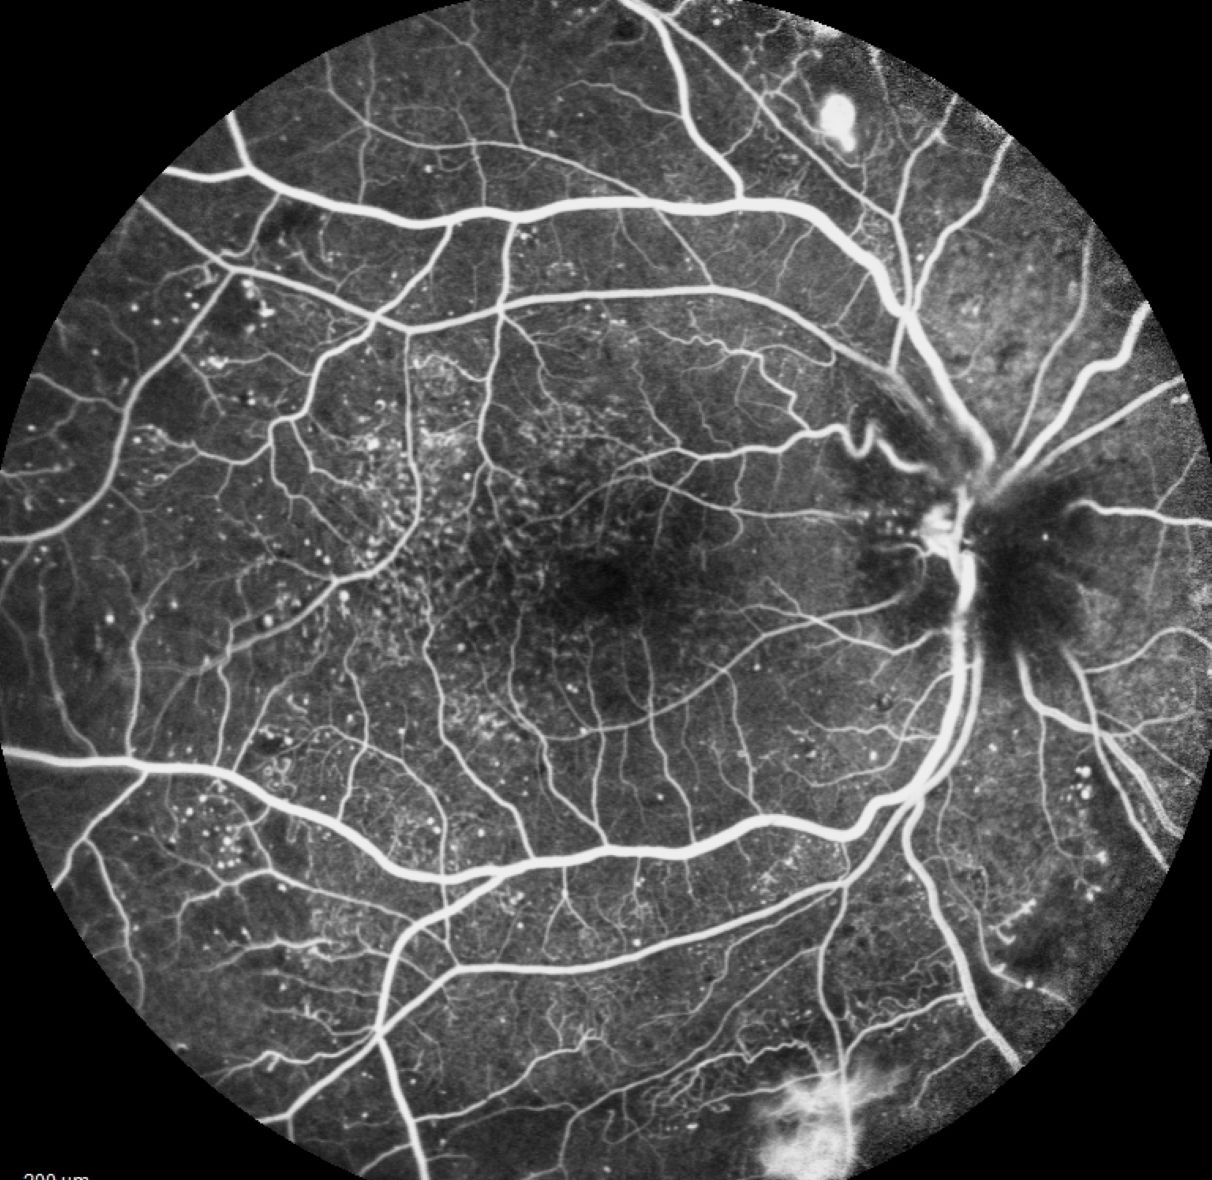

Nos ophtalmologistes assurent le diagnostic et le traitement de la DMLA, des occlusions veineuses et artérielles rétiniennes, de la vasculopathie polypoïdale, de la choriorétinopathie séreuse centrale, ainsi que des maladies rétiniennes génétiques et des dystrophies rétiniennes génétiques.

Pathologies maculaires

La macula, zone centrale de la rétine, est essentielle pour la précision visuelle, la lecture et la reconnaissance des visages.

Au centre PARIS RETINA VISION, nos spécialistes traitent l’ensemble de ces affections, de la maladie de Stargardt aux formes complexes comme l’ERD ou la VPC. Grâce à un plateau technique de pointe, nous assurons un diagnostic précis et un traitement adapté à votre pathologie.

Le centre est équipé d’un plateau technique complet et de dernière génération, permettant d’assurer le dépistage, le diagnostic précis et la prise en charge globale de l’ensemble des pathologies rétiniennes.

Qu’il s’agisse de la DMLA, du glaucome ou de toute autre affection de la rétine, nos équipements et notre expertise garantissent un accompagnement adapté à chaque patient.